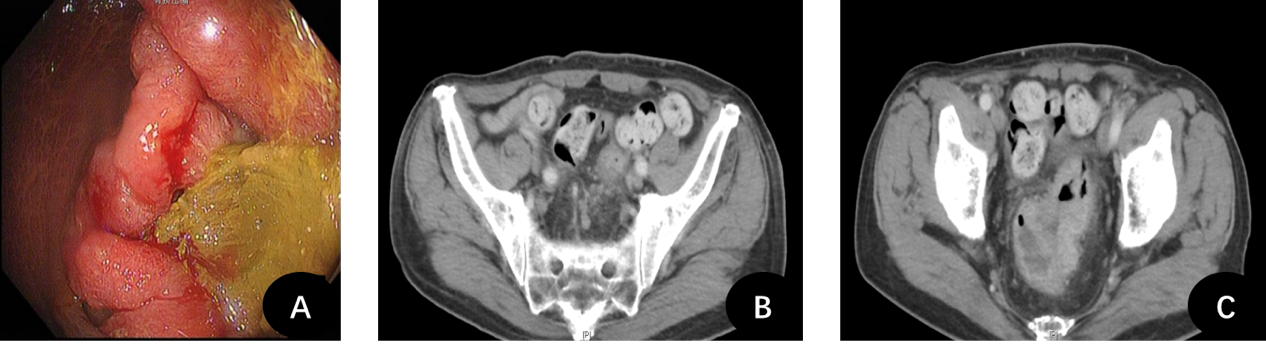

图A:肠镜提示直肠恶性肿瘤;B图+C图:CT显示直肠后方多发淋巴结肿大、直肠壁增厚,提示肿瘤分期晚、恶性程度高